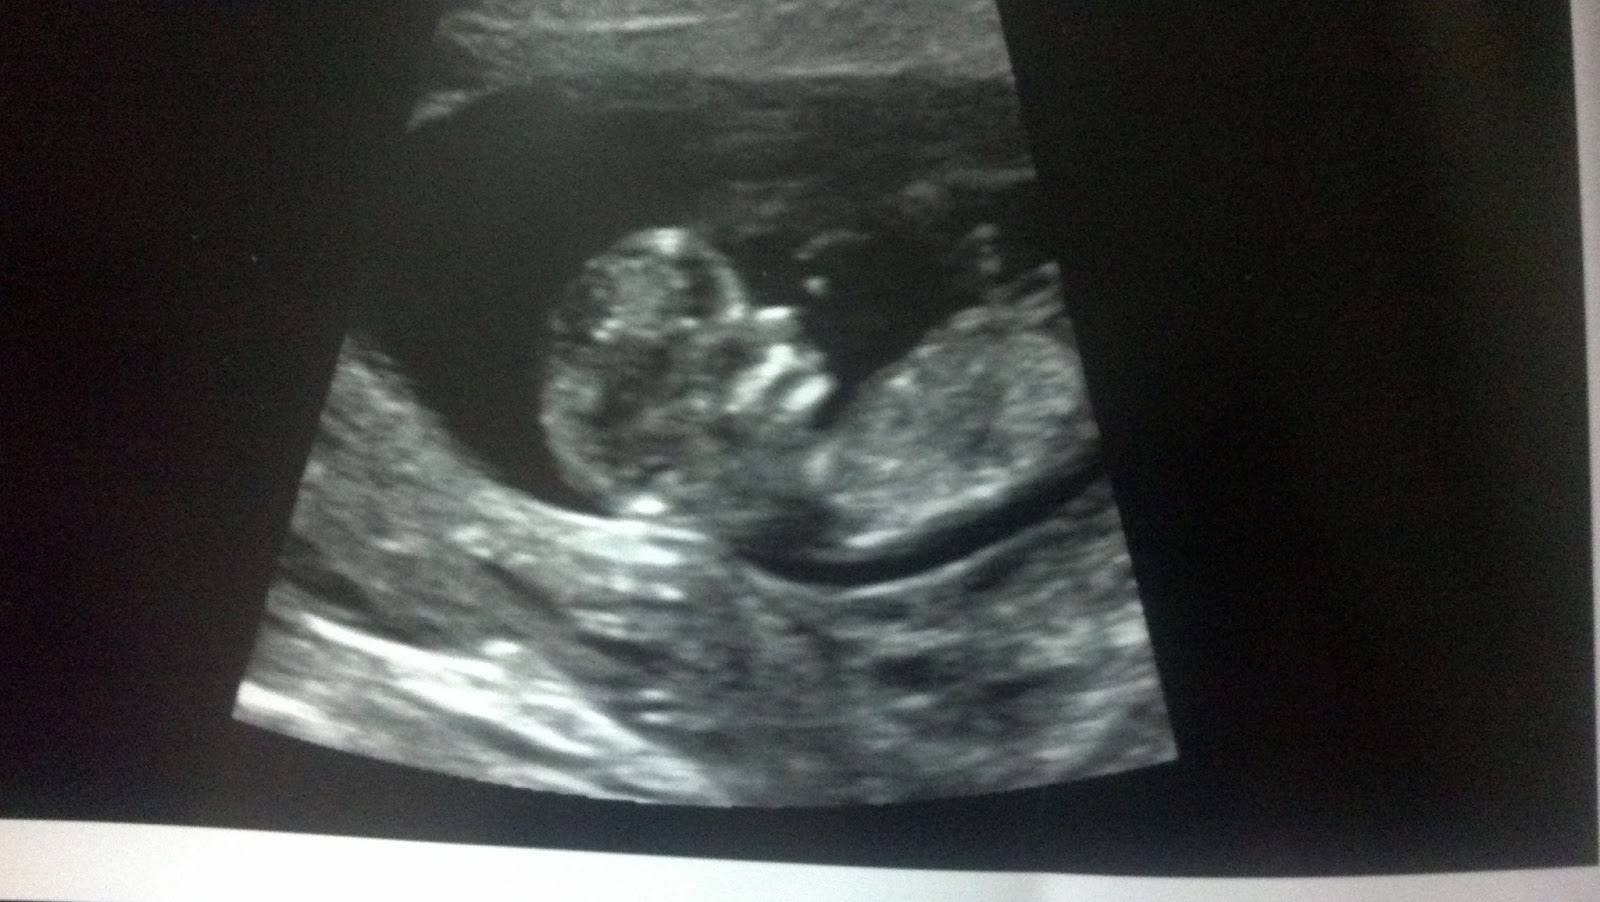

After that came the ultrasound. And there s/he was! You can see the little hand/fingers right up by the face.

The hands were up by the face the whole time (it looks like a little claw in the next picture), so it took a but of finagling to get him/her to move them a little, but all the markers for genetic issues were absent. S/he has a lovely nasal bone and a swanlike neck (nuchal fold was .78, normal is <3).